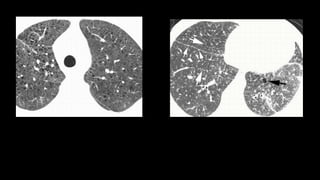

Findings?

USUAL INTERSTITIAL PNEUMONIA AND IDIOPATHIC PULMONARY FIBROSIS